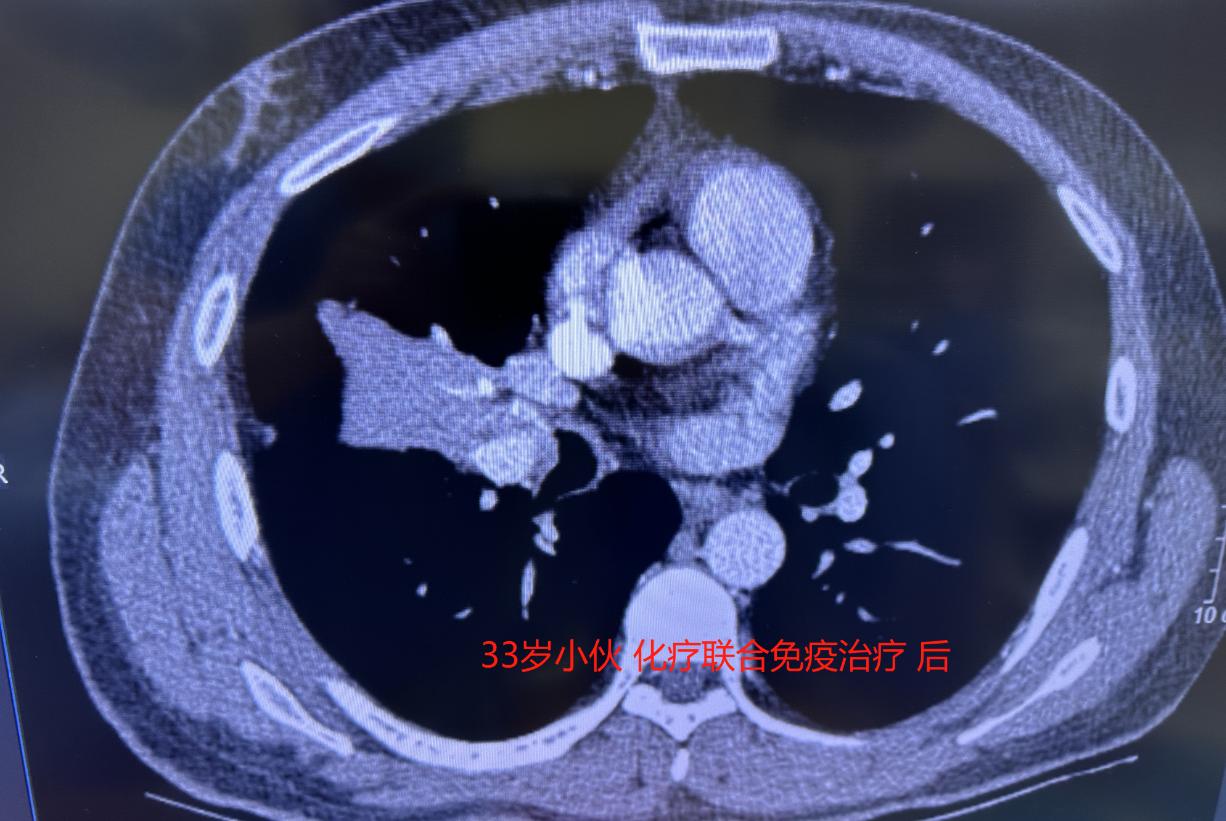

但没想到,三次治疗下来,肿瘤一点都没缩小——这个方案对他竟然没起作用。

既然药物治疗效果不好,我们团队商量后,决定直接手术。虽然风险大,但只有放手一搏,才可能有转机。手术采用微创胸腔镜,但因为肿瘤侵犯范围广,血管气管处理起来非常困难。

原本计划做袖状切除,但在手术中实际探查后,我们发现做“右肺中下叶联合切除”更稳妥、也更干净。于是术中果断调整了方案。

很庆幸,手术比预期还要顺利,肿瘤被完整切除了。